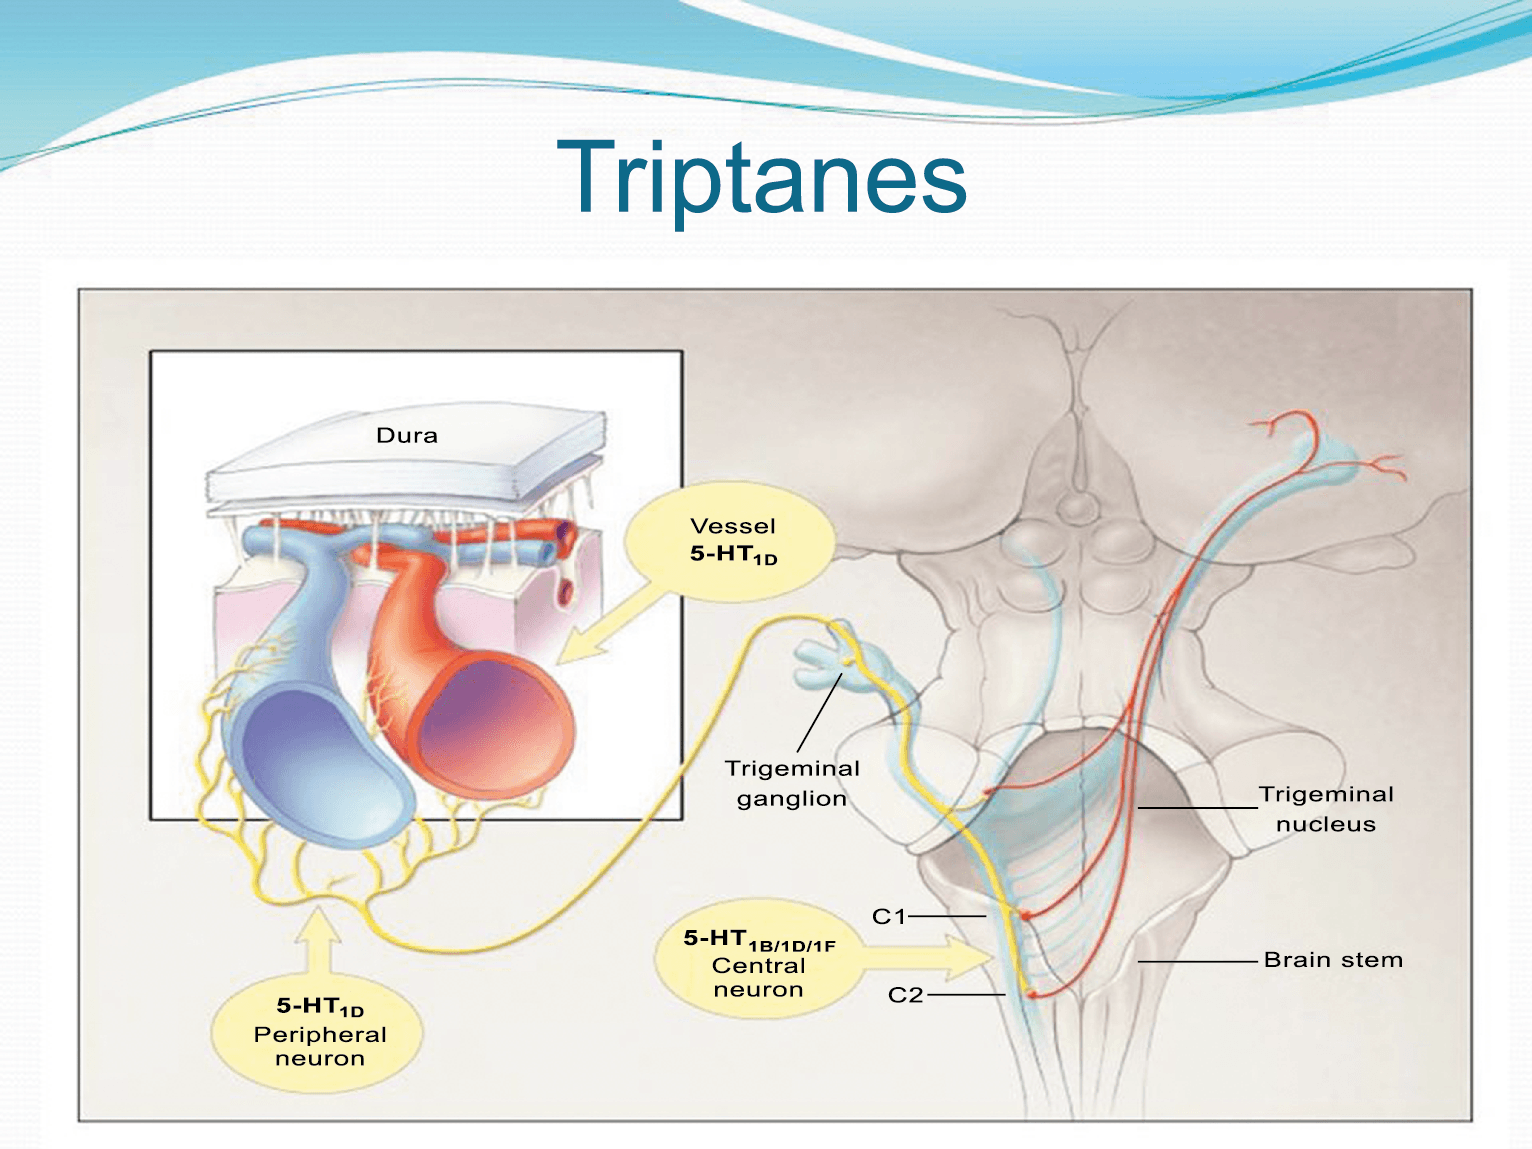

Hay una proyección aferente central desde el ganglio del trigémino que ingresa a la médula caudal del tronco encefálico, a través del tracto del trigémino, que termina en el núcleo espinal del trigémino caudalis (TNC), así como la médula espinal cervical superior (C1–C2). (Figura 16)

Las fibras nociceptivas Aδ y C terminan predominantemente en las láminas superficiales, I y IIo, así como en las láminas más profundas V–VI del TNC y extensión cervical. La estimulación de la vasculatura dural en modelos animales, incluidos los senos transverso y sagital superior y la arteria meníngea media, da como resultado la activación de las neuronas en las regiones TNC, C1 y C2 de la médula espinal cervical, conocidas en conjunto como el complejo trigeminocervical (TCC).

Estos datos sugieren que el núcleo del trigémino se extiende hasta el asta dorsal de la región cervical superior en un continuo funcional que incluye la extensión cervical, ello explica la distribución de la percepción del dolor en la migraña sobre las regiones frontal y temporal, además de la participación de parietal, occipital y regiones cervicales superiores(27).

Por lo tanto, se cree que la naturaleza intensa y pulsátil del dolor en la migraña es el resultado de la activación, o la percepción de activación, de estas entradas nociceptivas de las estructuras intracraneales y extracraneales, que convergen y se transmiten a través del TCC. (Figura 17)

Posteriormente diversos estudios demostraron que la infusión de 5-HT podría abortar tanto la cefalea inducida por reserpina(55) como la espontánea(56). En respuesta a estos estudios, el sistema del receptor 5-HT ganó mucha atención, lo que culminó con el descubrimiento de los triptanos, la serotonina y los agonistas del receptor 5-HT1B/1D(57). Todos exceptuando el 5-HT3 (canal iónico controlado por ligando) son receptores acoplados a proteína G. Si bien los triptanos se clasifican como agonistas de los receptores 5-HT1B/1D, la mayoría también activa en menor medida los receptores 5-HT1A, 5-HT1E o 5-HT1F(58). Originalmente, los triptanos se desarrollaron para actuar sobre la vasculatura craneal, una idea apoyada por sus claras acciones vasoconstrictoras(59) (Figura 25) y la expresión preferencial del receptor 5-HT1B en los vasos craneales más que en los periféricos(60).

Un mecanismo neural de los triptanos en las terminaciones del nervio trigémino periférico podría inhibir la liberación de neuropéptidos proinflamatorios y la vasodilatación dural neurogénica(63), lo cual era consistente con el tema en desarrollo de la migraña como una enfermedad neurovascular. (Figuras 26 y 27)

A pesar de la clara farmacología de los triptanos en el tratamiento de la migraña, su uso es limitado en pacientes con factores de riesgo cardíaco(61), lo que obliga a dirigirse a receptores que carecen de acción vasoconstrictora. Una de esas dianas es el receptor 5-HT1F, que es activado hasta cierto punto por algunos triptanos, como el naratriptán y no por otros, como el rizatriptán(62). (Tabla 2)